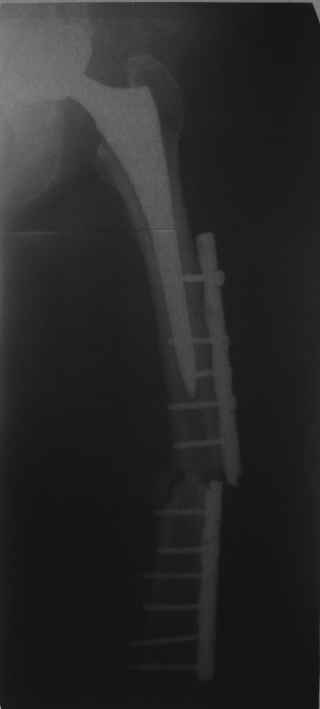

Обещанные ранее снимки Заранее спасибо.

Это сплошной титановый стержень. На дистальном конце отверстия под кондуктор. На другом - канал под ножку глубиной 60 мм, стенки толщиной 2,5-3 мм. И там же продольный пропил, чтобы канал мог адаптироваться к ножке.